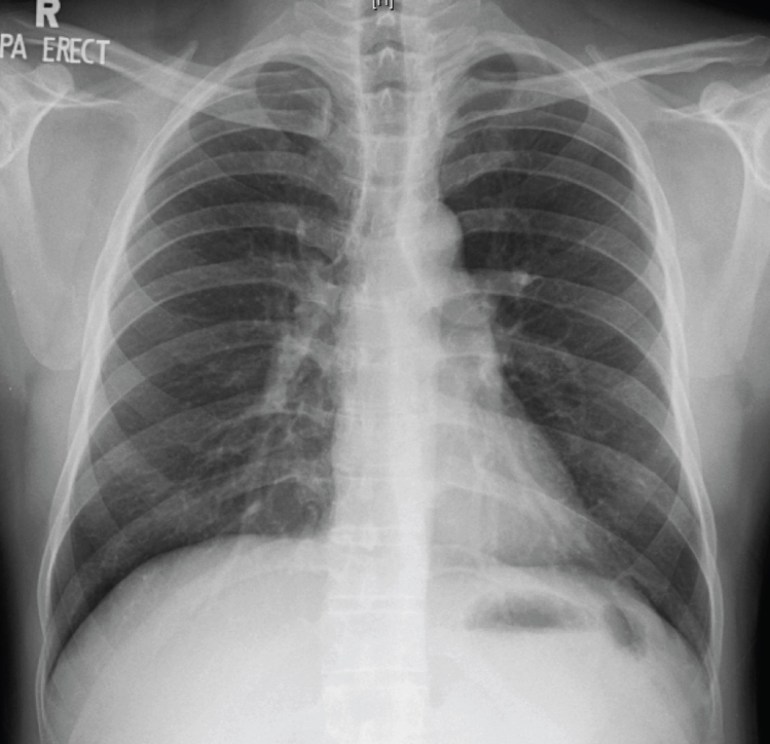

Clinical examination was unremarkable except for a drop in SpO2 to 92% after a brisk walk around the hospital room. The chest X-ray showed faint miliary shadows in both lung fields (the CXR image is provided below, but unfortunately the resolution is insufficient to permit visualisation of the abnormalities), which was confirmed on CT thorax.